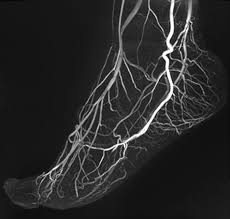

Und heute Morgen hatte ich einen Termin im Spital für ein peripheres Angiographie-MRI «Peripheral Angiography MRI», eine Untersuchung zur Vorbereitung der Operation Mitte November. Wie immer bei dieser Art von Bildgebung ist der Lärm des Geräts ohrenbetäubend: von schrillen Pfeiftönen über lautes Brummen bis zu ständigem Hämmern. Mit Kopfhörern und etwas Musik ist es erträglicher, aber fast zwei Stunden in dieser Röhre zu verbringen bleibt mühsam, auch wenn es nicht schmerzhaft ist. Um die Blutgefässe sichtbar zu machen, wurde mir während der Untersuchung ein Kontrastmittel injiziert. Diese Aufnahmen werden es ermöglichen, die Situation mit dem Bindegewebe einzuschätzen und die geeignete Operationstechnik zu bestimmen, um unerwünschte Blutungen zu vermeiden.